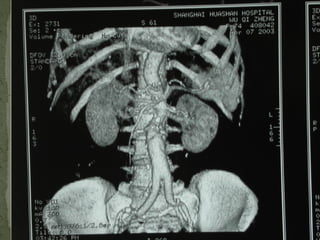

VR MPR MIP

10/20/15山血管外科网华 www.vascularcenter.cn 80

10/20/15山血管外科网华 www.vascularcenter.cn 81

10/20/15山血管外科网华 www.vascularcenter.cn 82

10/20/15山血管外科网华 www.vascularcenter.cn 84